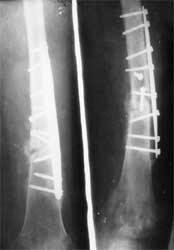

股骨骨折术后2年,骨不连形成

BMP复合骨髓注射2次,骨折愈合